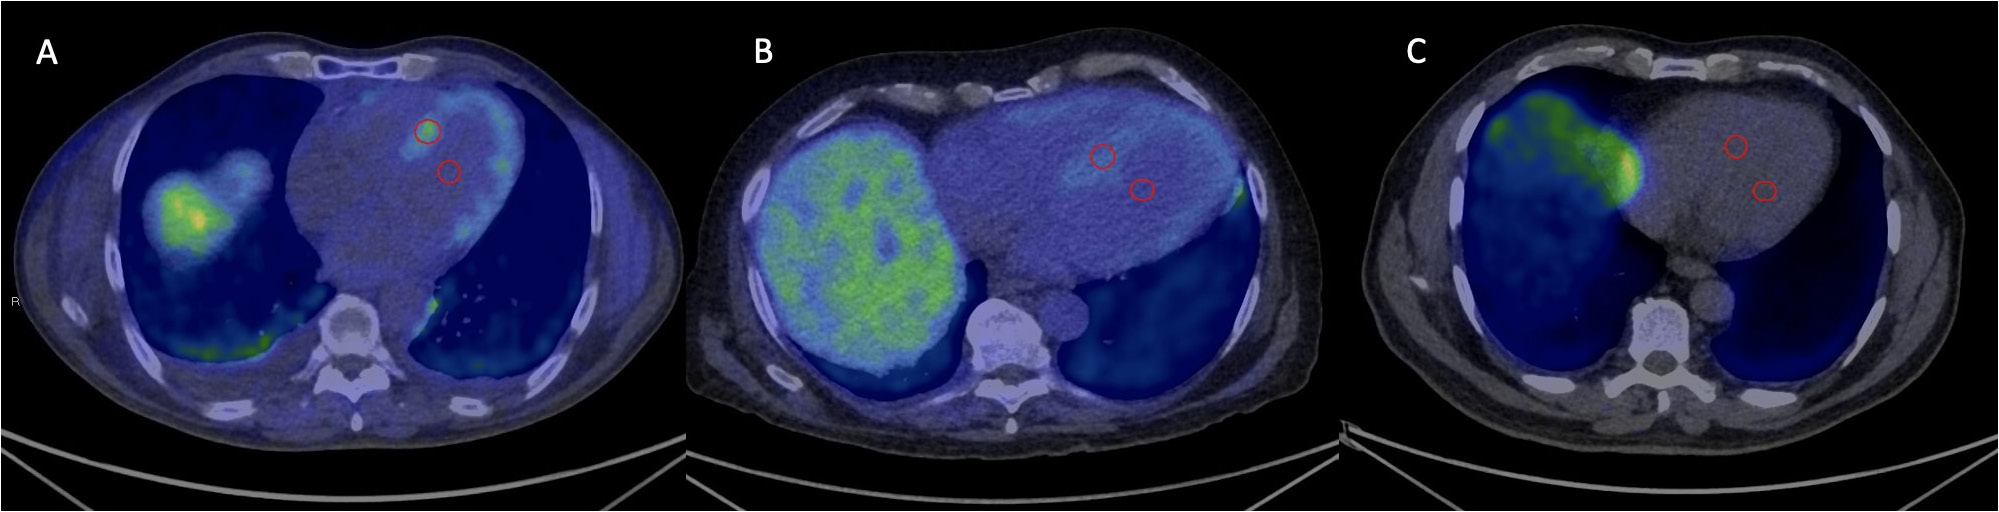

Radioisotope techniques

This section refers to Figure 4, Figure 5. Radioisotope techniques are currently the basic method for diagnosing ATTR-CA. The techniques employ the technetium (Tc)-99m radioisotope and the tracers classically used in the skeletal examination: 3,3-diphosphono-1,2 propanodicarboxylic acid (DPD); pyrophosphate (PYP); and methylenediphosphonic acid (MDP).43 However, scintigraphy is often available only in reference centers. The simplicity of imaging and a high specificity of nearly 100% (in the absence of light chains and monoclonal protein) for ATTR-CA are the advantages of scintigraphy emphasized by many authors.44, 45, 46 Currently, a semi-quantitative visual assessment is applied using the Perugini 4-point scale (0–3).44 The degree of isotope accumulation is compared to the flat sections of the ribs. What is characteristic of ATTR-CA is the diffuse uptake of the radioisotope in the myocardium. A complete scintigraphy analysis of the heart may also include the interpretation of the single-photon emission computed tomography (SPECT) perfusion as well as the calculation of the heart/contralateral lung (H/CL) index. This index is a quantitative comparison of the region of interest (ROI) ratio in the heart and the contralateral lung tested after 1 h (>1.5) or 3 h (>1.3).47 The observations of Gillmore et al. confirmed the considerable usefulness of scintigraphy with the abovementioned bone tracers.48 In the absence of monoclonal protein in serum or urine, and with the grade 2 or 3 uptake of the radioisotope, the specificity of the ATTR-CA diagnosis with this method was 100% in that publication. The authors concluded that it was unnecessary to perform an endomyocardial biopsy.48 Furthermore, Marume et al. assessed a combination of parameters to increase the pretest probability of scintigraphy.49

If the abovementioned proteins are not detected, the SPECT/CT examination is performed with the use of DPD or PYP labeled with technetium-99m (Tc-99m). Grade 2 or 3 uptake in the absence of light chains and monoclonal protein allows the diagnosis of ATTR-CA. In doubtful cases (scintigraphy grade 0–1), when both AL-CA and ATTR-CA are highly suspected, patients should be additionally referred for CMR or PET/CT. A myocardial biopsy and the analysis of amyloid protein composition using mass spectrometry should also be considered.